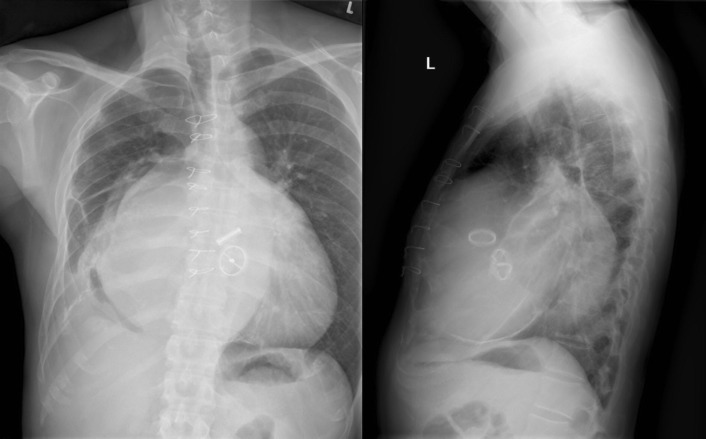

Pericardial Calcification

Pericardial calcification ( Figs. 27-1 to 27-4 ) is most prominent in the interventricular and atrioventricular grooves, and lateral to the right atrial and ventricular walls ( Graphic 27-1 ). When looking for pericardial calcification, it is necessary to scrutinize the lateral chest radiograph well, particularly the diaphragmatic surface. Pericardial calcification does not usually involve the left heart as much the right heart, and it does not often involve the apex (which, if calcified, is far more often due to prior infarction). Pericardial calcification should prompt serious consideration of the diagnosis of constrictive pericarditis, and clinicians should seek other radiographic and clinical features of constriction.